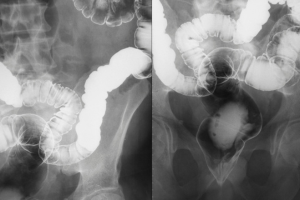

5

Identify abnormalities in the abdomen or other organs.